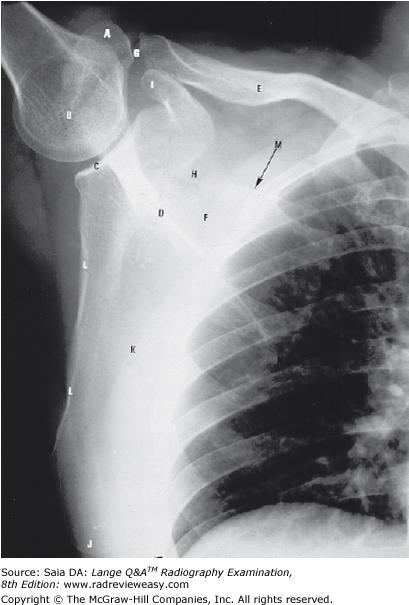

What is the structure indicated by the letter A in Figure 7–3?

A greater tubercle

B coronoid process

C coracoid process

D acromion process

-The radiograph illustrates an AP projection of the scapula; abduction of the arm moves the scapula away from the rib cage, revealing a greater portion of the scapula than would be visualized with the arm at the side. A number of bony structures are identified: the acromion process (A), the humeral head (B), glenoid fossa (C), scapular spine (D), clavicle (E), supraspinatus fossa (F), acromioclavicular joint (G), scapular notch (H), coracoid process (I), inferior angle/apex (j), body/costal surface (K), lateral/axillary border (L).